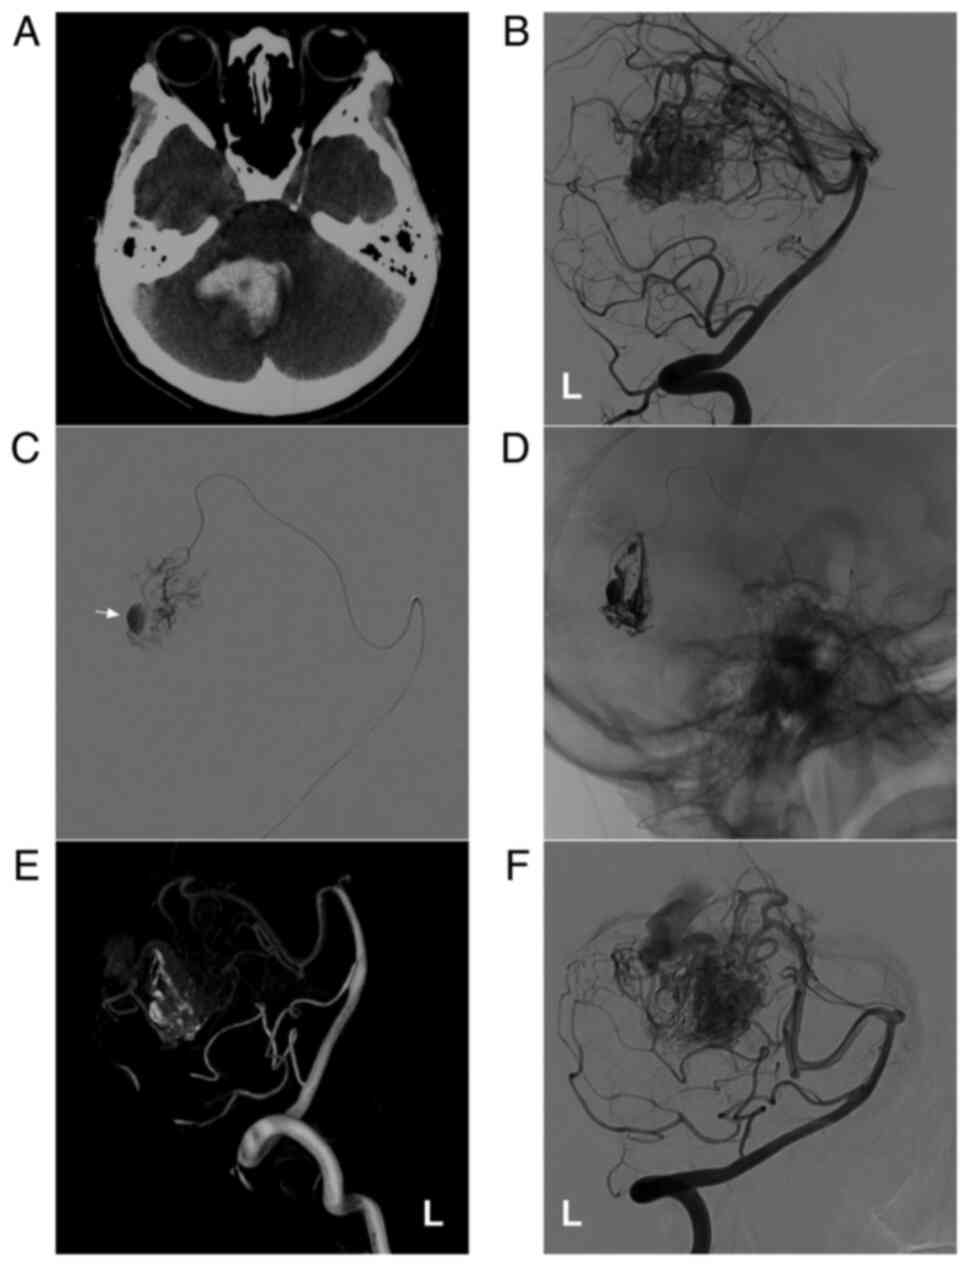

Figure 1

AVM in the upper cerebellum fed by the SCA alone. (A) Brain CT illustrating a left cerebellar hemispheric hemorrhage. (B) Brain CTA illustrating the left SCA (arrow) feeding the AVM (ellipse). (C) Microcatheter angiography via the SCA showing that the diffuse AVM drained through a superficial vein (star). (D) Microcatheter through the SCA (arrow) Onyx™ casting (ellipse). (E) DSA showing no imaging of the AVM following embolization. (F) Cerebellar hematoma drainage was performed following embolization, and the drainage tube (arrow) was observed. The case presented in this figure was a 30-year-old female. She had a sudden a headache and vomiting, and she was awake after onset. Following EVT, hematoma puncture and aspiration were performed. She recovered well. AVM, arteriovenous malformation; CT, computed tomography; CTA, computed tomography angiography; L, left; SCA, superior cerebellar artery.